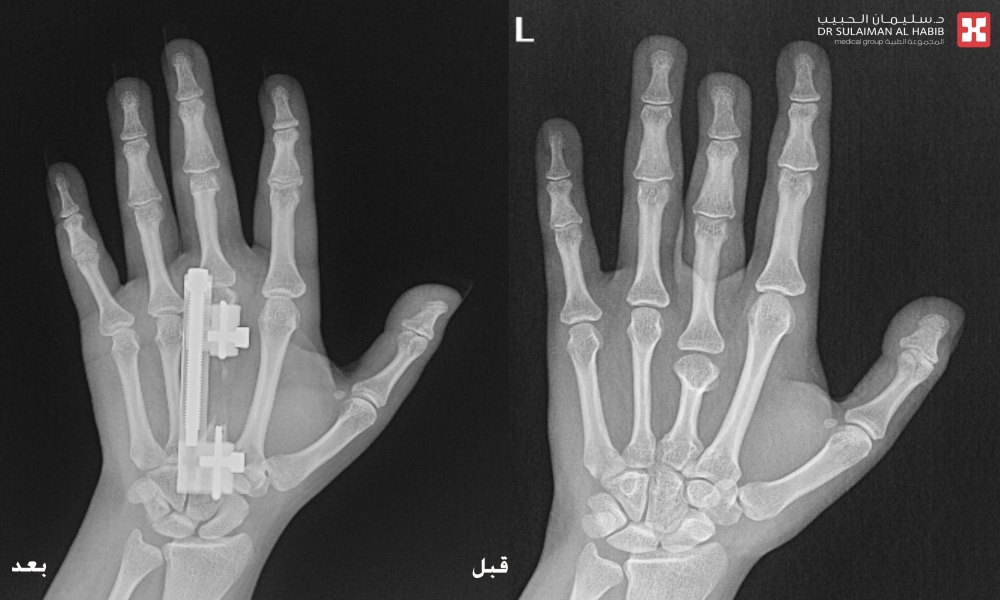

وقال د. الرفاعي أن المراجعة وصلت المستشفى في حالة نفسية معقدة، وبعد الإستماع إلى شكواها والإطلاع على ملفها الطبي، تم إخضاعها لمجموعة من الفحوصات الطبية والتي شملت، الأشعة المقطعية (C.T Scan) والسينية الرقمية (Digital X-Rays) والتحاليل المخبرية.

مشيراً إلى أن نتائج الفحوصات أوضحت وجود تشوه خلقي باليدين مع قصر بالإصبع الأوسط بأكثر من ٤ سم، بالإضافة إلى وجود ميلان وإنحسار بالحركه، وهو الأمر الذي أثر على الوظيفة الطبيعية لليد وبشكل كبير، فضلاً عن التأثير النفسي بسبب التشوه الظاهر. موضحاً أن الفريق الطبي المعالج قام بدراسة كافة النتائج، واضعاً خطة يتم فيها تطويل الإصابع.

وأوضح الدكتور الرفاعي أن العملية استغرقت ساعتين ونصف، وتم فيها استخدام تقنية التطويل والتعديل التدرجي بإستخدام جهاز Super Mini LRS ، والذي يتميز بسهولة الإستخدام، وصغر الحجم كي لا يتسبب في الإزعاج خاصة فترة الليل أو عند الحركة، نقلت بعدها المراجعة إلى جناح التنويم، للمتابعة الحثيثة، وعلى إثر تحسن حالتها خرجت من المستشفى بعد يومين وهي بصحة جيدة، مع وضع برنامج دوري لزيارة العيادة ومتابعة نتائج التطويل.

وأكد د. الرفاعي أن اليد أصبحت طبيعية تماماً من الناحية الوظيفية والشكلية ولله الحمد، مشيداً بتوفر الأجهزة والتقنيات المتقدمة لعلاج حالات التشوه العظمي، موضحاً أن حالة المراجعة، تُعد من الحالات النادره والمعقده، وذلك لوجود شبكات من الأوعية الدموية والأعصاب والأوتار المحيطة بمنطقة اليد، والتي تتطلب خبره عاليه ودقه بإجراء هذه الجراحات.